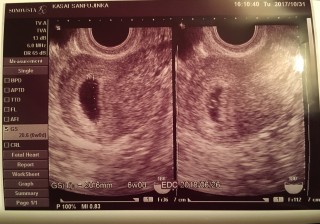

写真:5w4d:チャイさん

子宮内に無事着床してることがわかりました!胎嚢の大きさ的に5週半ばくらいですね〜とのこと!

卵黄嚢?みたいなものも少し見えてました!エコー写真には写ってないけど汗

次は7週くらいの時に診察予定です!

心拍確認できますように!